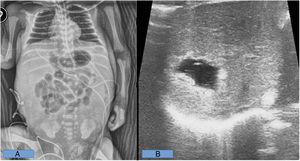

Caso 1. Varón prematuro de 29+6 semanas ingresado en la UCI neonatal por prematuridad y distrés respiratorio. Portador de catéter umbilical desde el ingreso, usándose del segundo al quinto día para nutrición parenteral. El quinto día se retira por adecuada tolerancia enteral. En el sexto día de vida se contacta con Cirugía Pediátrica para valorar distensión abdominal y edematización de la pared rápidamente progresiva. El paciente requiere soporte respiratorio invasivo y soporte vasoactivo. Durante el seguimiento clínico se realizan radiografías abdominales seriadas sin neumoperitoneo ni signos de enterocolitis. Se evidencia ascitis progresiva con asas centralizadas y colapsadas. Los estudios analíticos tampoco son concordantes con enterocolitis. El séptimo día persisten dichos hallazgos. Se realiza ecografía que evidencia: trombosis portal izquierda, lesión focal quística en segmento iva del lóbulo izquierdo hepático compatible con extravasación y ascitis moderada-severa con septos y focos ecógenos móviles en su interior (no se descartan hallazgos de enterocolitis). Ante la gravedad clínica y la duda diagnóstica se coloca drenaje abdominal con salida inmediata de abundante ascitis de aspecto lechoso, compatible con nutrición parenteral extravasada. El paciente presenta una evolución posterior favorable, siendo extubado y retirándose el drenaje abdominal a los 2 días, no presentando más incidencias abdominales.

Caso 2. Mujer prematura de 31+4 semanas ingresada en la UCI neonatal por prematuridad y distrés respiratorio con evolución favorable. El noveno día de vida presenta hipotensión, anemia y distensión abdominal rápidamente progresiva. Se decide laparotomía urgente tras el fracaso de las medidas médicas de reanimación. Se evidencia un hemoperitoneo masivo, con restos de nutrición parenteral, secundario a un estallido hepático derecho. Se observa laceración hepática de 8cm en los lóbulos vii-viii, con otra mínima laceración a nivel lateral del segmento vi, ambas con sangrado activo. El eje vascular portal estaba íntegro y la hipoperfusión intestinal era generalizada. Se establece como causa del estallido hepático la extravasación intraparenquimatosa de la nutrición parenteral administrada por vía umbilical. Se llevan a cabo distintas técnicas hemostáticas sin éxito, finalizando la intervención con un packing abdominal para revisión posterior. En las horas siguientes la paciente presenta empeoramiento clínico, fracaso multiorgánico y finalmente exitus (figs. 1 y 2).